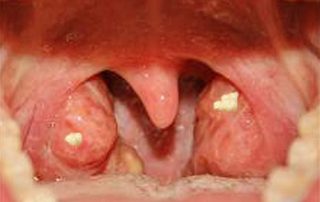

سنگ لوزه

سنگ لوزه Tonsillolith [...]